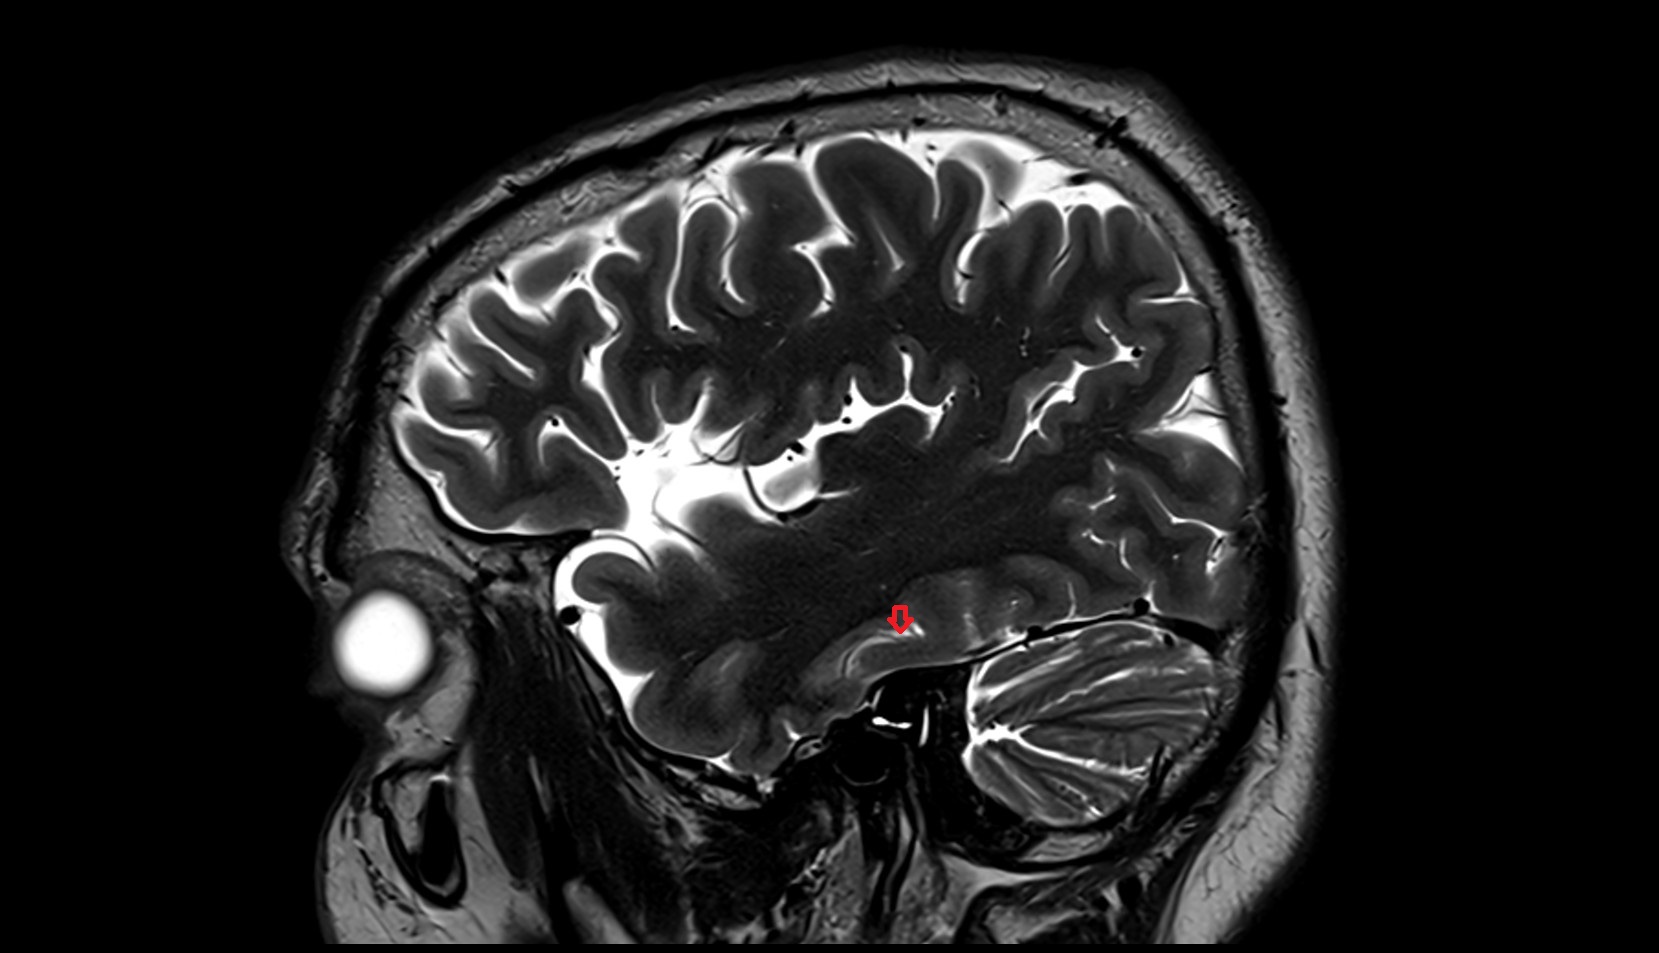

- Mammillary body

- Pituitary gland

- Pituitary stalk

- Pineal gland